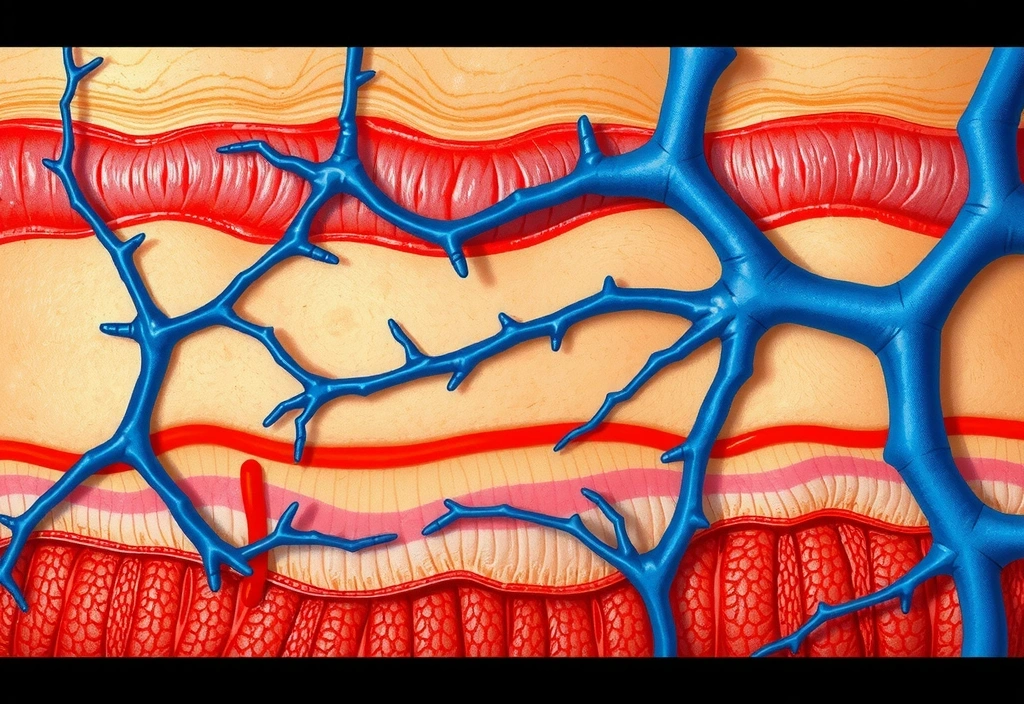

Understanding the science is key to effective anti-aging. Our skin naturally produces collagen and hyaluronic acid, crucial for its firmness and hydration. With age, this production declines, leading to visible signs of aging. Our creams are formulated to replenish these vital components and stimulate the skin's natural regenerative processes.